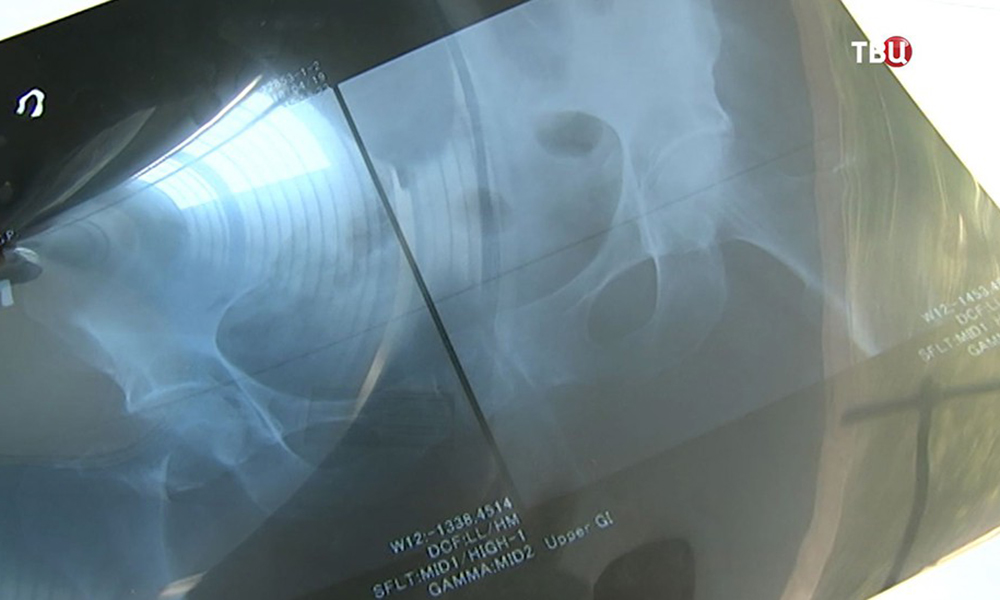

В больнице имени Иноземцева успешно сделали операцию 99-летнему пациенту

27.07.2018

Пожилой пациент сломал шейку бедра накануне своего 100-летнего юбилея. Шел из магазина, на лестничной площадке оступился и упал. Хорошо, что соседи помогли! Хирурги проделали поистине ювелирную работу – установили больному современный эндопротез.